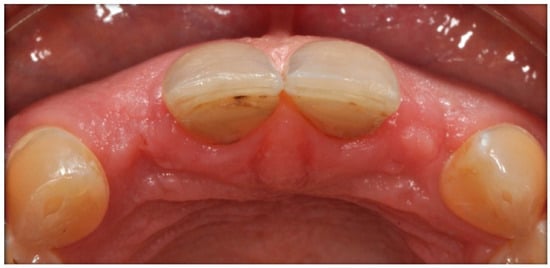

The case describes rehabilitating two congenitally missing lateral incisors in a young patient (38 years old) undergoing orthodontic treatment to create the necessary space for implant placement (Figure 1 and Figure 2). Two fibre-reinforced composite Maryland bridges (Tender Fiber Quattro—Micerium) were utilised for provisional rehabilitation (Figure 3, Figure 4 and Figure 5). Two Osstem TSIII 3.5 × 10.0 implants (1.5 mm subcrestal), two straight Osstem Zirconia abutments, and two-layered lithium disilicate crowns were employed for the definitive restoration (Figure 5, Figure 6, Figure 7, Figure 8, Figure 9, Figure 10, Figure 11, Figure 12, Figure 13, Figure 14, Figure 15, Figure 16, Figure 17, Figure 18, Figure 19 and Figure 20) [,]. The dental implant position was planned after a three-dimensional radiographic analysis in a prosthetically guided way. Patient rehabilitation was performed with an immediate post-surgery provisional (Maryland-type, cemented with a resinous cement) application. Subsequently, a delayed loading of the new provisional dental implant was retained (cemented with zinc oxide eugenol cement) and finally, definitive crowns (cemented with a definitive resinous cement) on Osstem® abutments were installed (3 months).

Figure 2. Agnesia of 1.2–2.2. Initial case; occlusal view.